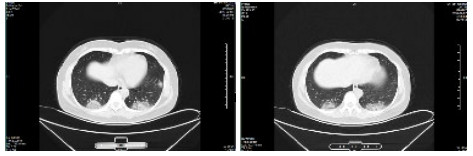

| 图 1 病例1,男性,65岁,沪籍,否认武汉流行病学接触史,发病前2周内每天有大型医院陪护史及疲劳史,既往体健,发热1 d入院,体温38.5℃,无咳嗽症状,无鼻塞,流涕,血白细胞总数及淋巴计数正常,甲乙型流感病毒筛查阴性,新型冠状病毒核酸检测阳性。肺部CT提示双肺多发磨玻璃结节,病灶贴近胸膜,局部小叶间隔增厚,炎症沿支气管血管走向分布,散在小结节影及纤维条索影 Fig 1 Case 1, male, 65 years old, born in Shanghai, denied the history of epidemic exposure of Wuhan. He had a history of accompanying in hospital every day and fatigue in the first two weeks before the onset of the disease. He was hospitalized one day after the onset of fever, with a body temperature of 38.5 ℃, no cough, no nasal obstruction and runny nose, normal WBC and lymph count, negative influenza A and B virus screening, and positive novel coronavirus nucleic acid test. Lung CT showed multiple ground glass nodules in both lungs. The focus was close to pleura, the interlobular septum was thickened, the inflammation distributed along the direction of bronchi and blood vessels, scattered in small nodule shadow and fibrous cord shadow |